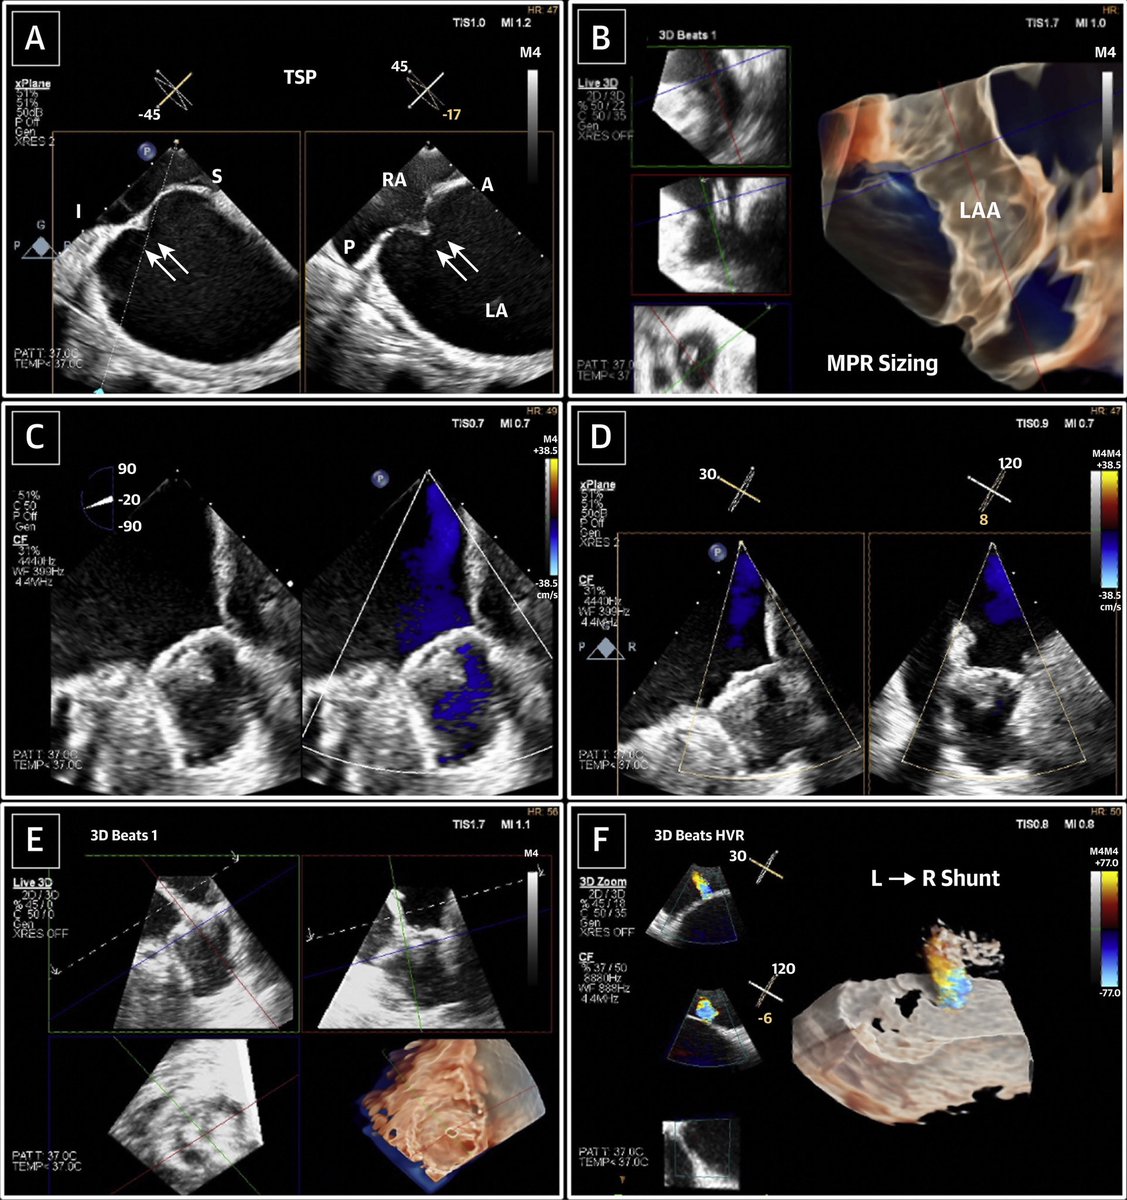

Complementary roles for intracardiac echo and TEE for edge to edge repair of complex tricuspid valve anatomy authors.elsevier.com/a/1c%7EJO6uPJv… JACC Journals Mayo Clinic CV